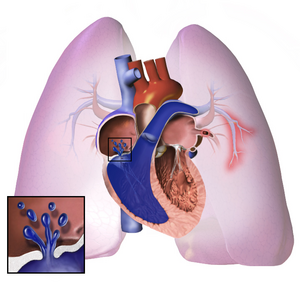

فرط ضغط الدم الرئوي. | |

فرط ضغط الدم الرئوي Pulmonary Hypertension، هو زيادة ضغط الدم داخل الشريان الرئوي أو الوريد الرئوي أو الشعيرات الدموية الرئوية (جميعها تعرف بالأوعية الرئوية أو أوعية الدورة الدموية الصغرى)، وزيادة الضغط في هذه الأوعية يؤدي إلى ظهور بعض الأعراض كضيق النّفس، الدوار، الاغماء، تورّم القدم والعديد من الأعراض الأخرى، التي تتفاقم جميعها مع ازدياد المجهود الجسدي. من الممكن أن يكون فرط ضغط الدّم الرئوي شديد جداً، مما يؤدي إلى قلة تحمل الجسم للتمارين الرياضيّة، تماماً كما يحدث في حالات الفشل القلبي.